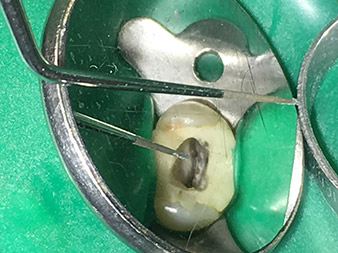

Dr. Nouraie: For me, ultrasonic endodontics is an optimal complement to the techniques previously available. Use of the expanded W&H endo tip range makes it possible to improve the quality of the treatment and thus the long-term prognosis for the teeth substantially. The quality of the tips is exceptionally high and absolutely worth recommending.

I find the abrasion performance particularly impressive, as it remains constant even after frequent use. In addition, the instruments can also be reprocessed very simply and cost-effectively.

Thank you for that enlightening discussion!